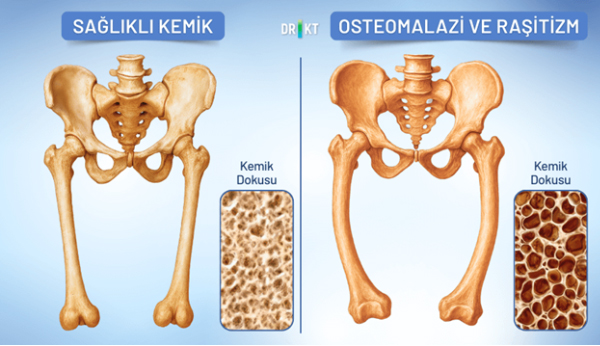

استئوپنی و پوکی استخوان

استئوپنی کاهش تراکم مواد معدنی استخوان به کمتر از حد طبیعی برای سن است و پیشآهنگ پوکی استخوان محسوب میشود. پوکی استخوان وضعیتی است که در آن ساختار داخلی استخوانها ضعیف و اسفنجی میشود. در نتیجه، استخوانها به اندازهای ضعیف می شوند که حتی با یک زمین خوردن ساده نیز می شکنند. استئوپنی و پوکی استخوان زمانی رخ میدهند که سرعت تشکیل استخوان بدن با سرعت تجزیه آن هماهنگ نباشد، در زنان در دوران پس از یائسگی و در بزرگسالان مسن شایعتر است. اگرچه کاهش تراکم استخوان اغلب باعث درد نمیشود، اما استخوانها را در برابر شکستگی آسیبپذیر میکند و محیطی مساعد برای درد استخوان ایجاد میکند.

شکستگیهای فشاری در ستون فقرات میتواند منجر به کمردرد، کاهش قد و به مرور زمان، قوز کردن بدن شود.

استئومالاسی و راشیتیسم

استئومالاسی نرم شدن استخوانها به دلیل معدنی شدن ناکافی و کمبود شدید ویتامین D و کلسیم در بزرگسالان است. راشیتیسم معادل کودکی این بیماری است.

راشیتیسم بر صفحات رشد استخوانها تأثیر میگذارد و منجر به استخوانهای ضعیف و نرم میشود. علت اصلی هر دو مشکل، پوکی استخوان ناشی از سطح ناکافی ویتامین D به دلیل کمبود نور خورشید است که برای جذب کلسیم ضروری است و یا کمبودهای تغذیهای است علائم رایج پوکی استخوان شامل درد و حساسیت در باسن، کمر، پاها و لگن است.